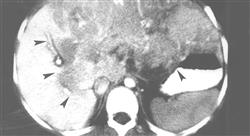

أخبار تشخيصية وعلاجية عن التقييم والتشخيص والتدخل في أورام الجهاز الهضمي

التصوير السريري وتصوير الإختبارات والصور لأغراض التشخيص

الحصول على معلومات محدثة عن أورام الكبد الصفراوي وتأثيراتها على الجهاز الهضمي